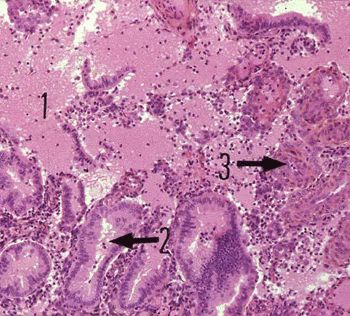

Phase menstruelle utérine

(Photo : webapps.fundp.ac.be)

• un retour à la normale du tonus vasculaire qui provoque un éclatement des parois des capillaires (3) et une hémorragie massive (globules rouges en quantité en 1). Les glandes tubulaires sont déformées (2).